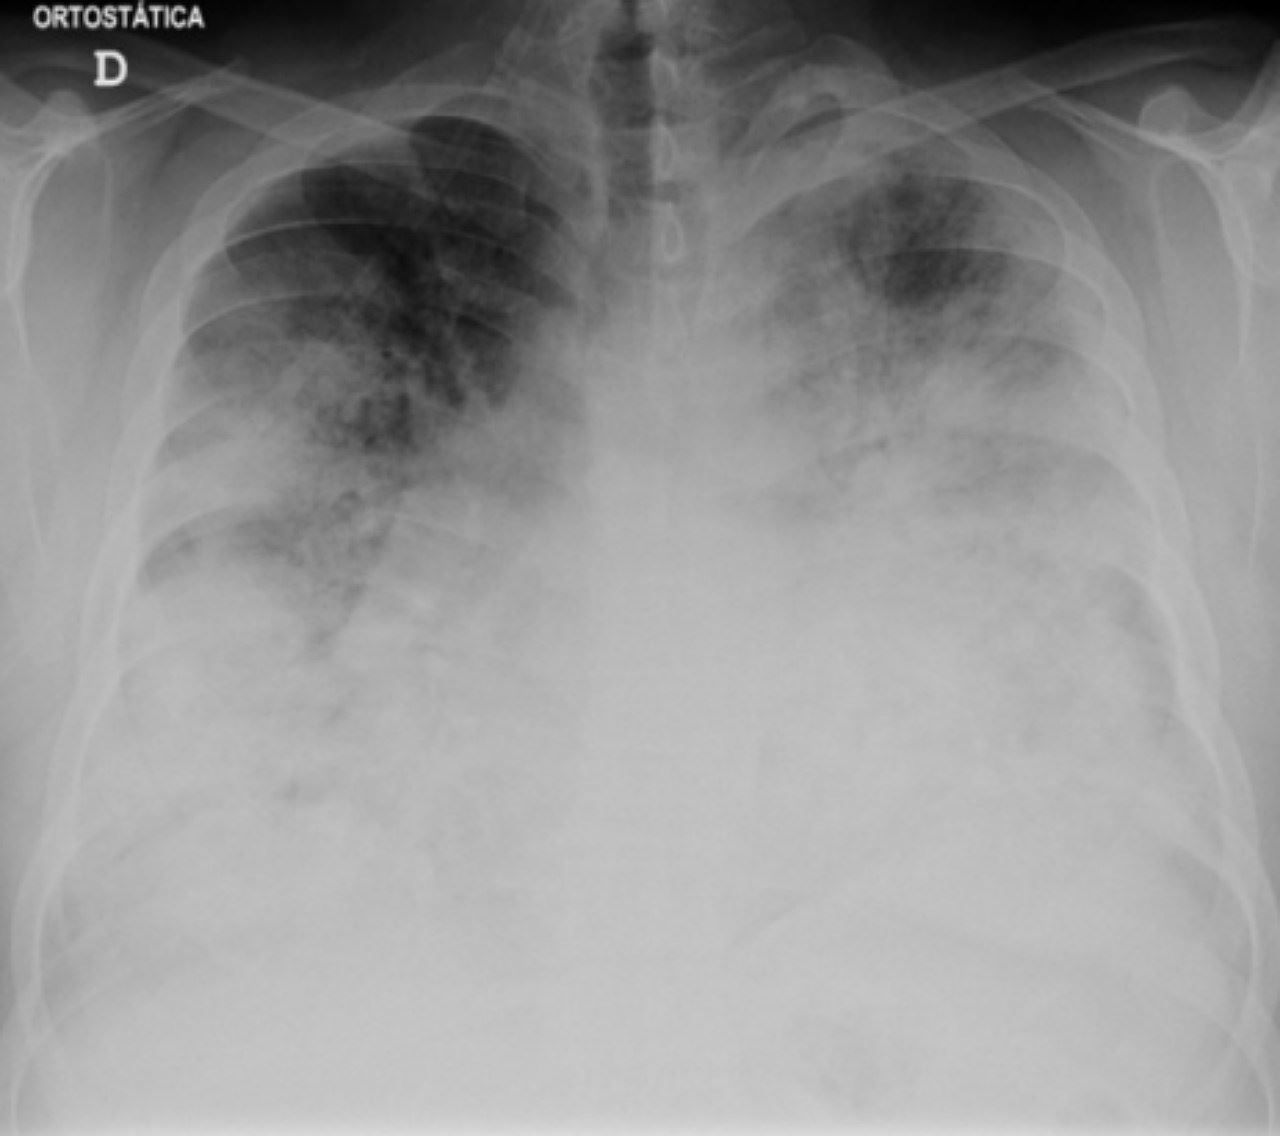

Penyakit Legionnaires merupakan pneumonia tahap serius yang disebabkan bakteria Legionella. Mereka yang menghirup udara yang mengandungi titis air atau secara tidak sengaja menelan air yang dicemari Legionella boleh jatuh sakit. Bagaimanapun, penyakit itu boleh dirawat dengan antibiotik dan tidak menjangkiti dari manusia ke manusia lain.

Antara simptom wabak ini adalah pneumonia, gangguan respiratori, demam, seram sejuk, batuk, pendek nafas, sakit otot dan sakit kepala.